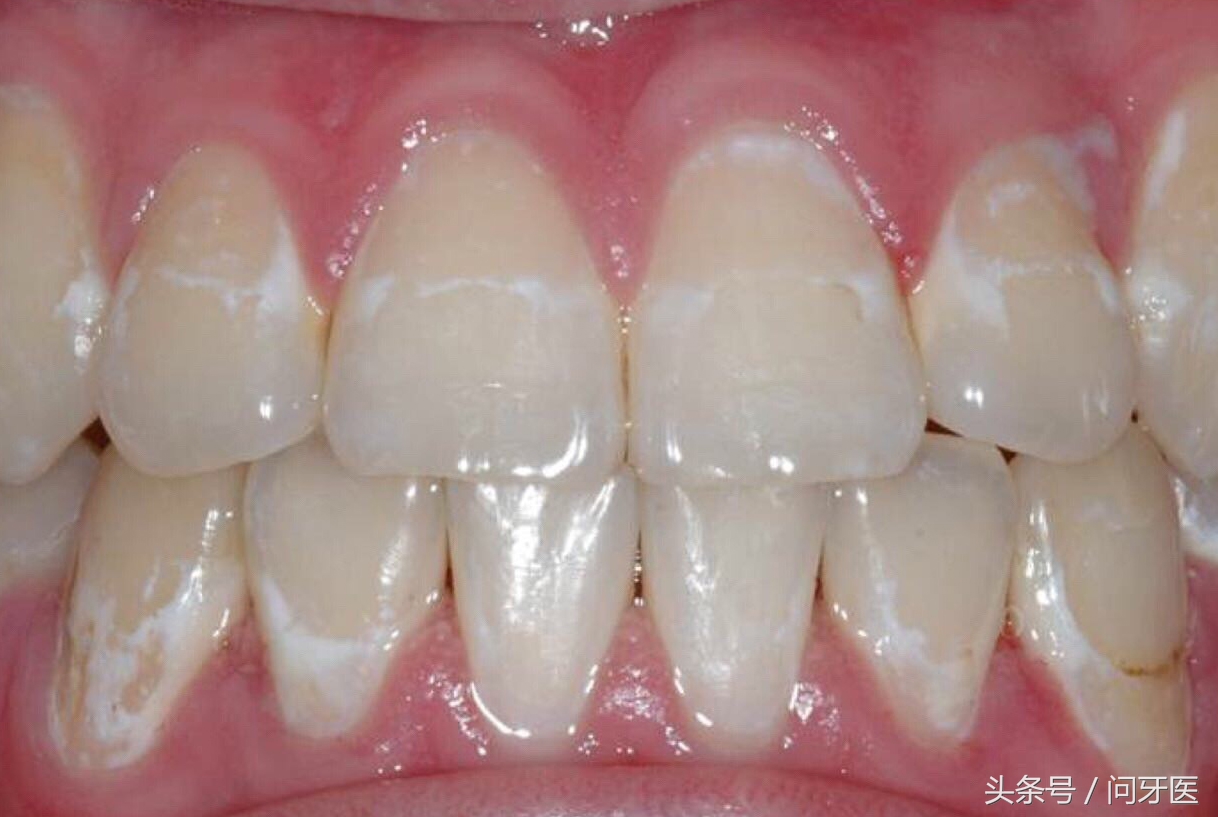

上图这种类型,叫做龋白斑,是牙釉质脱矿的表现。这是由于细菌附着在牙齿表面,分解出来的酸,使牙釉质脱矿。钙盐从牙釉质中减少,就形成了白垩色的斑块。

这就是蛀牙的前期征兆,慢慢发展下去白斑的地方就会掉块,形成蛀洞。可发生于多颗,也可局部单颗发生,主要发生在污垢细菌容易附着的地方。